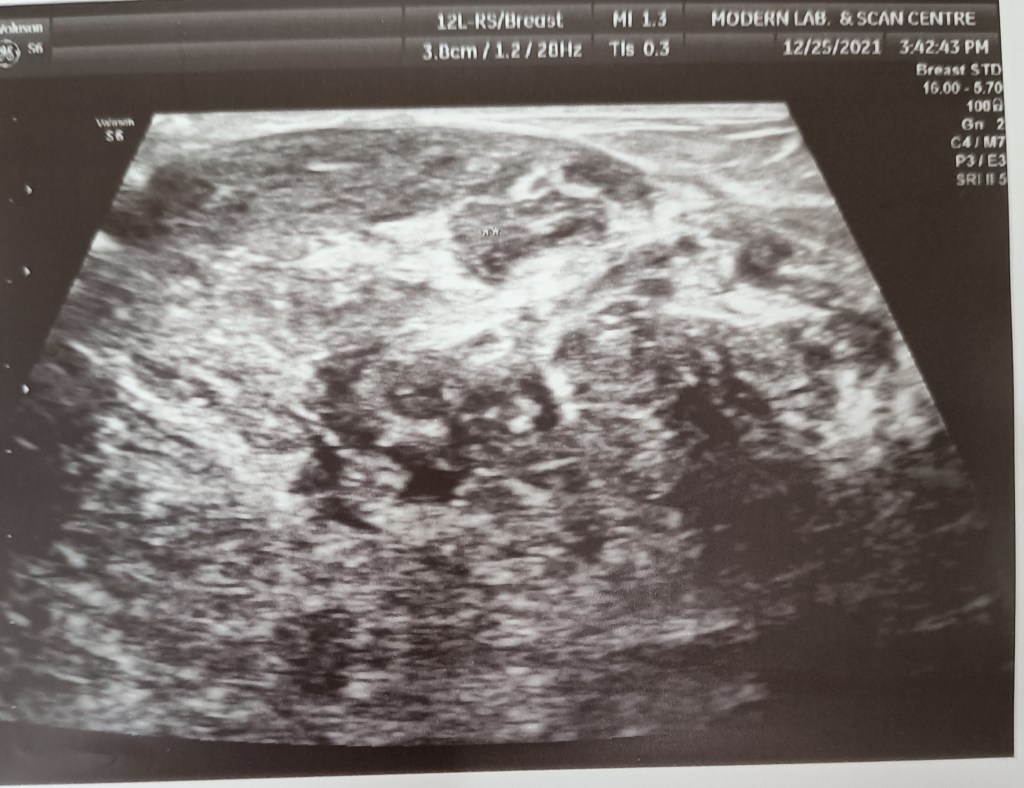

A big phyllodes tumor of the right breast removed at a simple total mastectomy (Dr Jagga’s case).